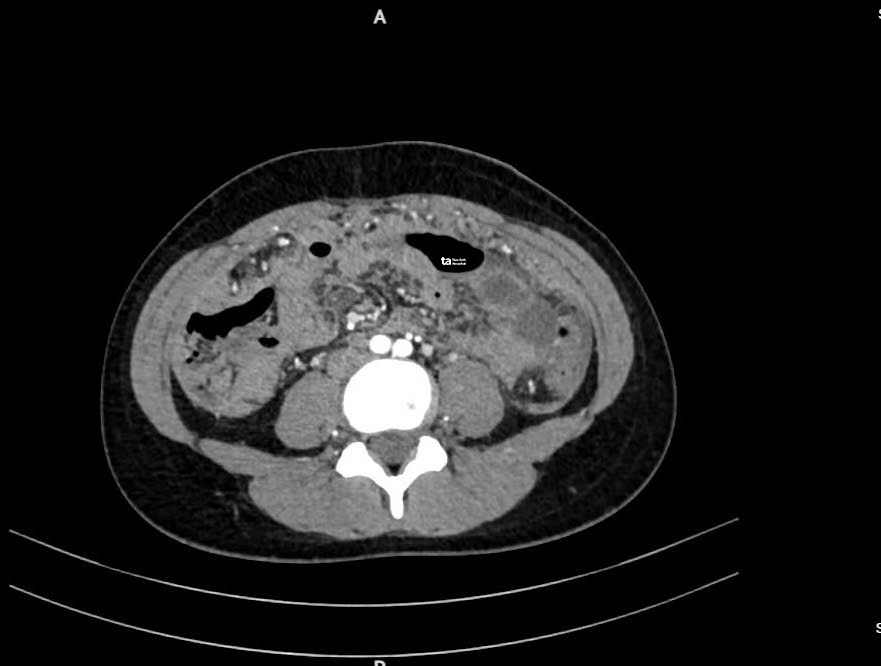

Ảnh cắt lớp vi tính (CT) cho thấy dịch chứa đầy ổ bụng (khoảng màu trắng). Ảnh: Bệnh viện Đa khoa Tâm Anh

Chị Hà được bác sĩ một bệnh viện chẩn đoán viêm ruột,nghi ngờ lao ruột,chỉ định theo dõi. Sau đó chị đau bụng nhiều hơn kèm buồn nôn,sốt,cơ thể lạnh run,siêu âm và chụp CT tại Bệnh viện Đa khoa Tâm Anh TP HCM cho thấy nhiều dịch trong ổ bụng. Các bác sĩ hút ra khoảng hai lít dịch màu vàng nhạt trong bụng của chị Hà. ThS.BS.CKI Lưu Xuân Phát,Trung tâm Nội soi và Phẫu thuật Nội soi Tiêu hóa,cho biết đây là nguyên nhân khiến người bệnh tăng cân dù chán ăn. Sau khi hút hết dịch,các triệu chứng trên bắt đầu giảm.